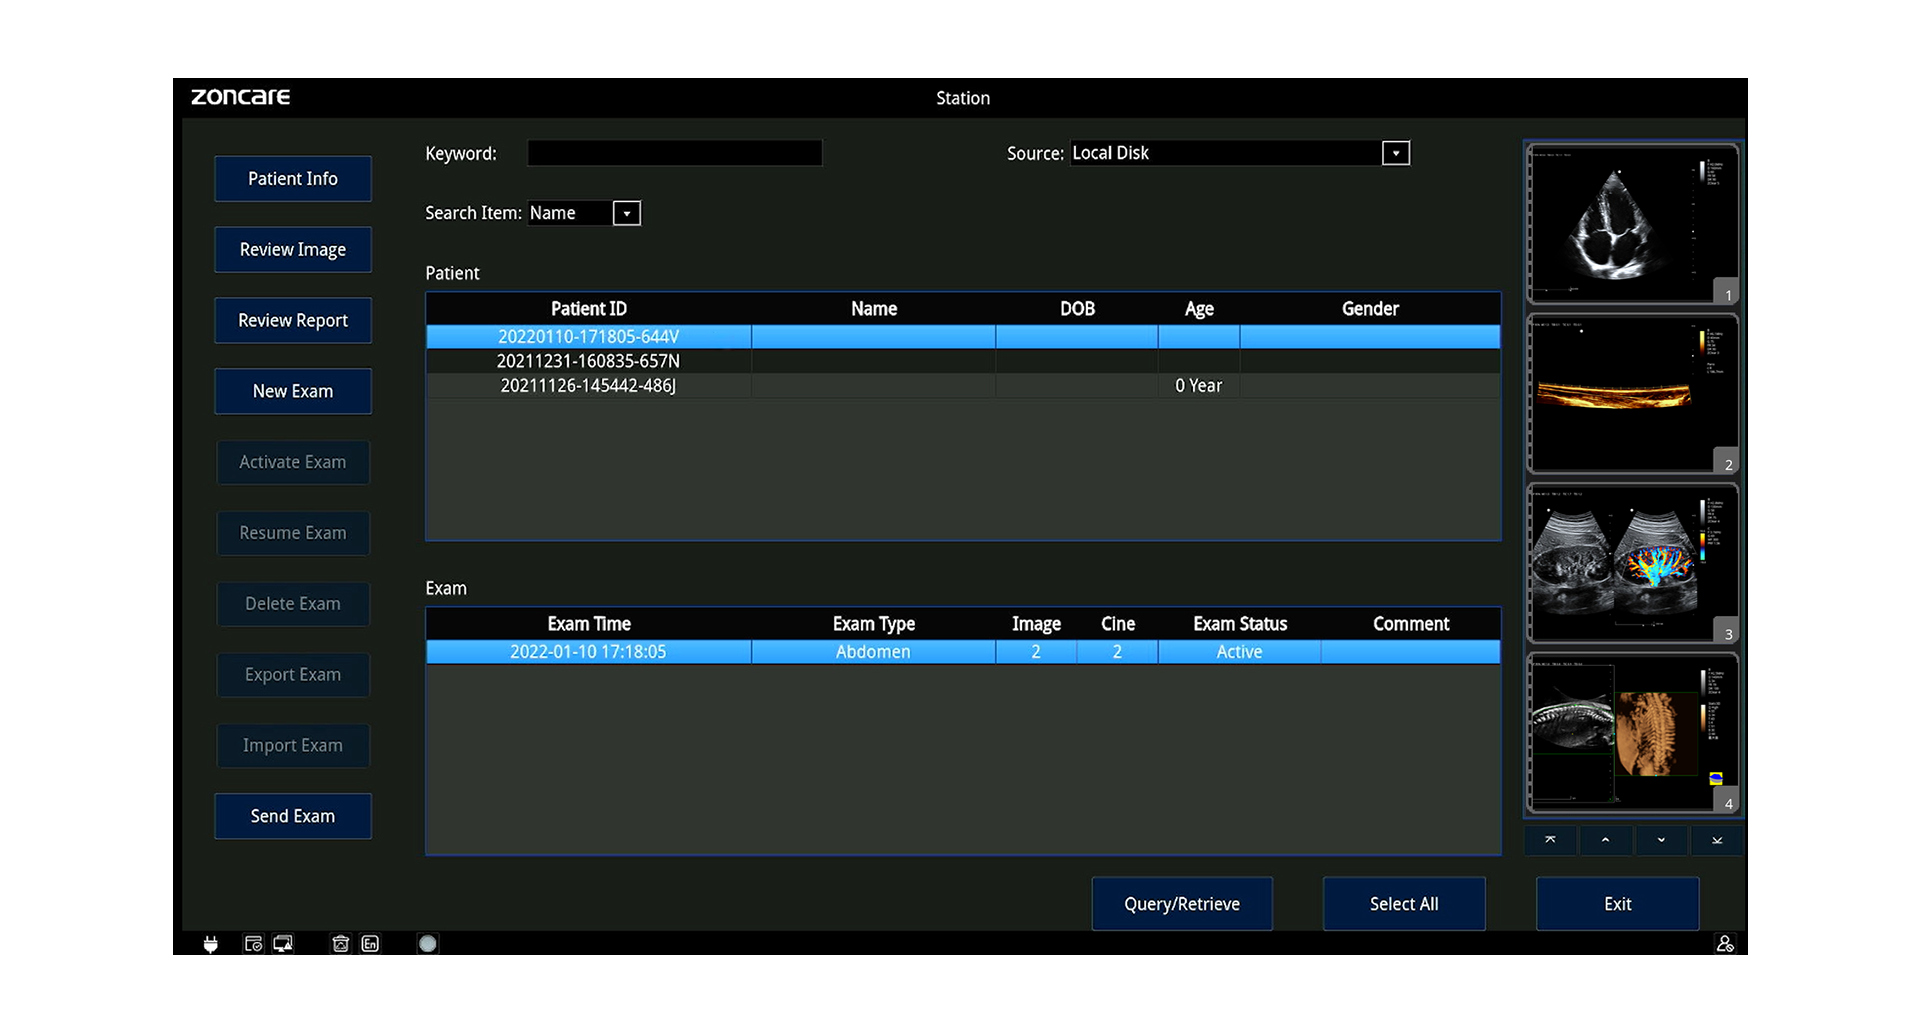

Almacenamiento, Datos y Conectividad

-

Disco interno: 1 TB

-

Formatos: RAW, DICOM, JPG, BMP, TIFF, AVI, MP4

-

DICOM 3.0 (Storage, Worklist, MPPS, Query/Retrieve, etc.)

-

Wi-Fi, Bluetooth, LAN, envío a PC

-

Teleconsulta remota, control inverso y docencia en vivo

-

Informes exportables a PDF (con opción de ocultar datos del paciente)